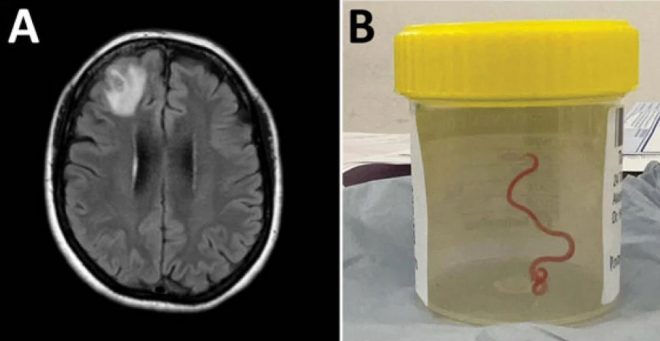

Nevrokirurg Hari Priya Bandi je pacientki iz glave izvlekel dolgega parazitskega okroglega črva, nakar je poklical svoje kolege in jih prosil za nasvet, kaj naj naredi naprej, piše Guardian.

Slikanje z magnetno resonanco je pokazalo nepravilnosti, ki zahtevajo operacijo. Presenetljivo odkritje je spodbudilo ekipo v bolnišnici, da se je zbrala, da bi ugotovila, za kakšno vrsto gliste gre, in kar je najpomembneje, da bi se odločila, kakšno nadaljnje zdravljenje bi bolnica morda potrebovala.

Pacientka v bolnišnici v Canberri je prvi človek na svetu, pri katerem so našli tega parazita. Zdravniki pravijo, da se takšno odkritje zgodi enkrat v karieri. Pacientkino okrevanje zaenkrat poteka dobro, njeno stanje redno spremljajo.